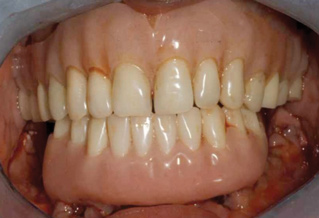

Fig 7. Existing dentition was sound periodontally and reasonably esthetic.

Figure 7

Interceptive implant therapy may then become a consideration earlier in life to create restorations that will not be subject to the latent effect of dental caries as aging continues. An example is shown in Figure 6 and Figure 7; the panoramic film of a 56-year-old man shows several orthognathic and extensive dental procedures historically. All full-coverage restorations had been replaced for a second time, and, again, all evidenced recurrent caries, but the existing dentition was periodontally sound and relatively esthetic.

The choice of removing a caries-challenged but restorable dentition at a younger age is ethically complex. Ultimately, the decision is the patient's alone based on informed consent of all available options. The removal of a potential lifetime of caries activity that is now more predictable than ever may be a viable option for this high-risk segment of a younger patient base.